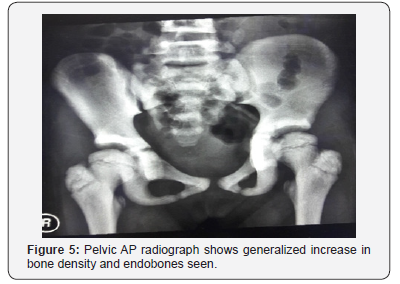

On examination, her height is at the fiftieth centile. There are no abnormal facies, no cranial anomalies, no frontal bossing, no hydrocephalus, no abnormal eye moments/ nystagmus. No bruises, purpura and no pallor seen. Abdominal examination reveals no hepatosplenomegaly. Her hemoglobin was 10.5 (low), hematocrit 34, WBC 6.13 and platelets 381. Serum calcium and phosphate levels were normal, alkaline phosphatase elevated. Plain radiographs reveal rugger- jersey appearance of her spine (Figure 4), “end bones” seen within her pelvis (Figure 5) and chest radiograph shows generalized increase in bone density (Figure 6).

The Autosomal Dominant osteopetrosis (ADO)/adult type, is also known as Albers-Schonberg disease. Sufferers are usuallyasymptomatic. Some may develop scoliosis and multiple bone fractures. Based on the basis of radiographic, biochemical, and clinical features, there are two types of adult osteopetrosis. Type I is associated with low fracture risk and normal serum acid phosphate. Radiographically, the spine and pelvis are relatively normal and only the skull shows marked sclerosis mainly at the vault. Type II on the other hand is associated with high risk of fracture and very high serum acid phosphate levels. Radiographically, skull shows sclerosis mainly at the base, spine shows rugger- jersey appearance and endobones are seen in the pelvis